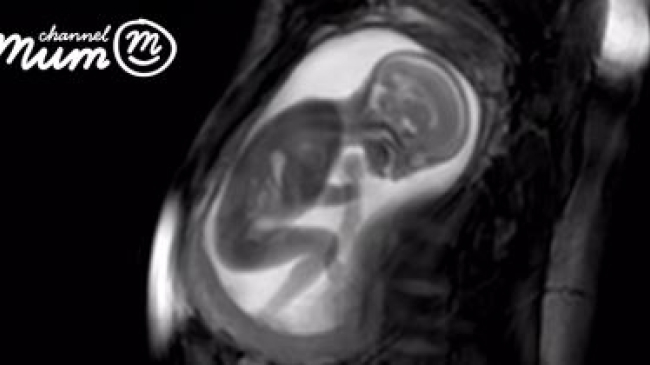

На видео, снятом лондонскими медиками при помощи аппарата магнитно-резонансной томографии, можно увидеть, чем занят ещё не рождённый ребёнок, сообщает Лайф.ру.

Команда лондонских медиков из проекта iFIND (Improving Fetal Imaging and Diagnosis, в переводе на русский – "Улучшение визуализации и диагностики плода") показала, на что способен новый аппарат магнитно-резонансной томографии (МРТ). С его помощью им удалось снять видео, на котором чётко видно, чем занимается 20-недельный ребенок в животе мамы. Можно даже разглядеть, как бьётся у него сердце.

Чтобы оценить размер человеческого плода, можно присмотреться к его бьющемуся сердцу. Оно размером всего с пятидесятикопеечную монету. Сам ребёнок имеет длину от 14 до 16 сантиметров и весит около 250 граммов.